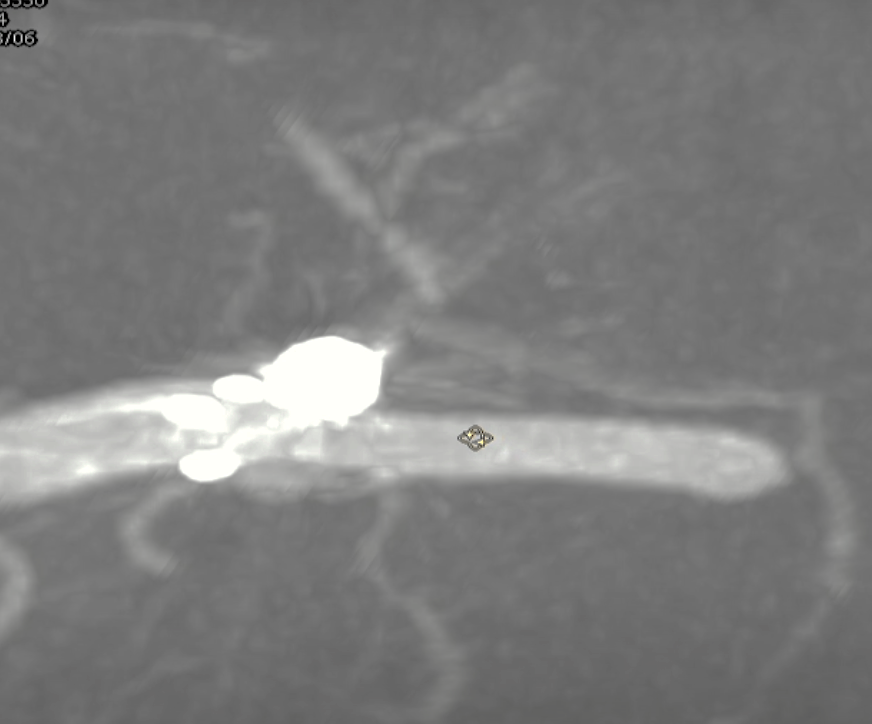

术后支架重建:支架打开良好,近端Marker位于颈内动脉分叉处

术后Vaso CT未见出血,患者神清语利,神经系统查体阴性。

继续填入Target 1.5/2弹簧圈成篮,后完全释放支架,其近端位于颈内动脉分叉处,远端位于A1远端。

术后正侧位造影:Raymond Ⅲ级